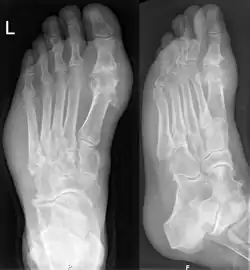

Gout may be diagnosed and treated without further investigations in someone with hyperuricemia and the classic acute arthritis of the base of the great toe (known as podagra). Synovial fluid analysis should be done if the diagnosis is in doubt.[17][51] Plain X-rays are usually normal and are not useful for confirming a diagnosis of early gout.[5] They may show signs of chronic gout, such as bone erosion.[47]

Gout on X-rays of a left foot in the metatarsal-phalangeal joint of the big toe. Note also the soft tissue swelling at the lateral border of the foot.